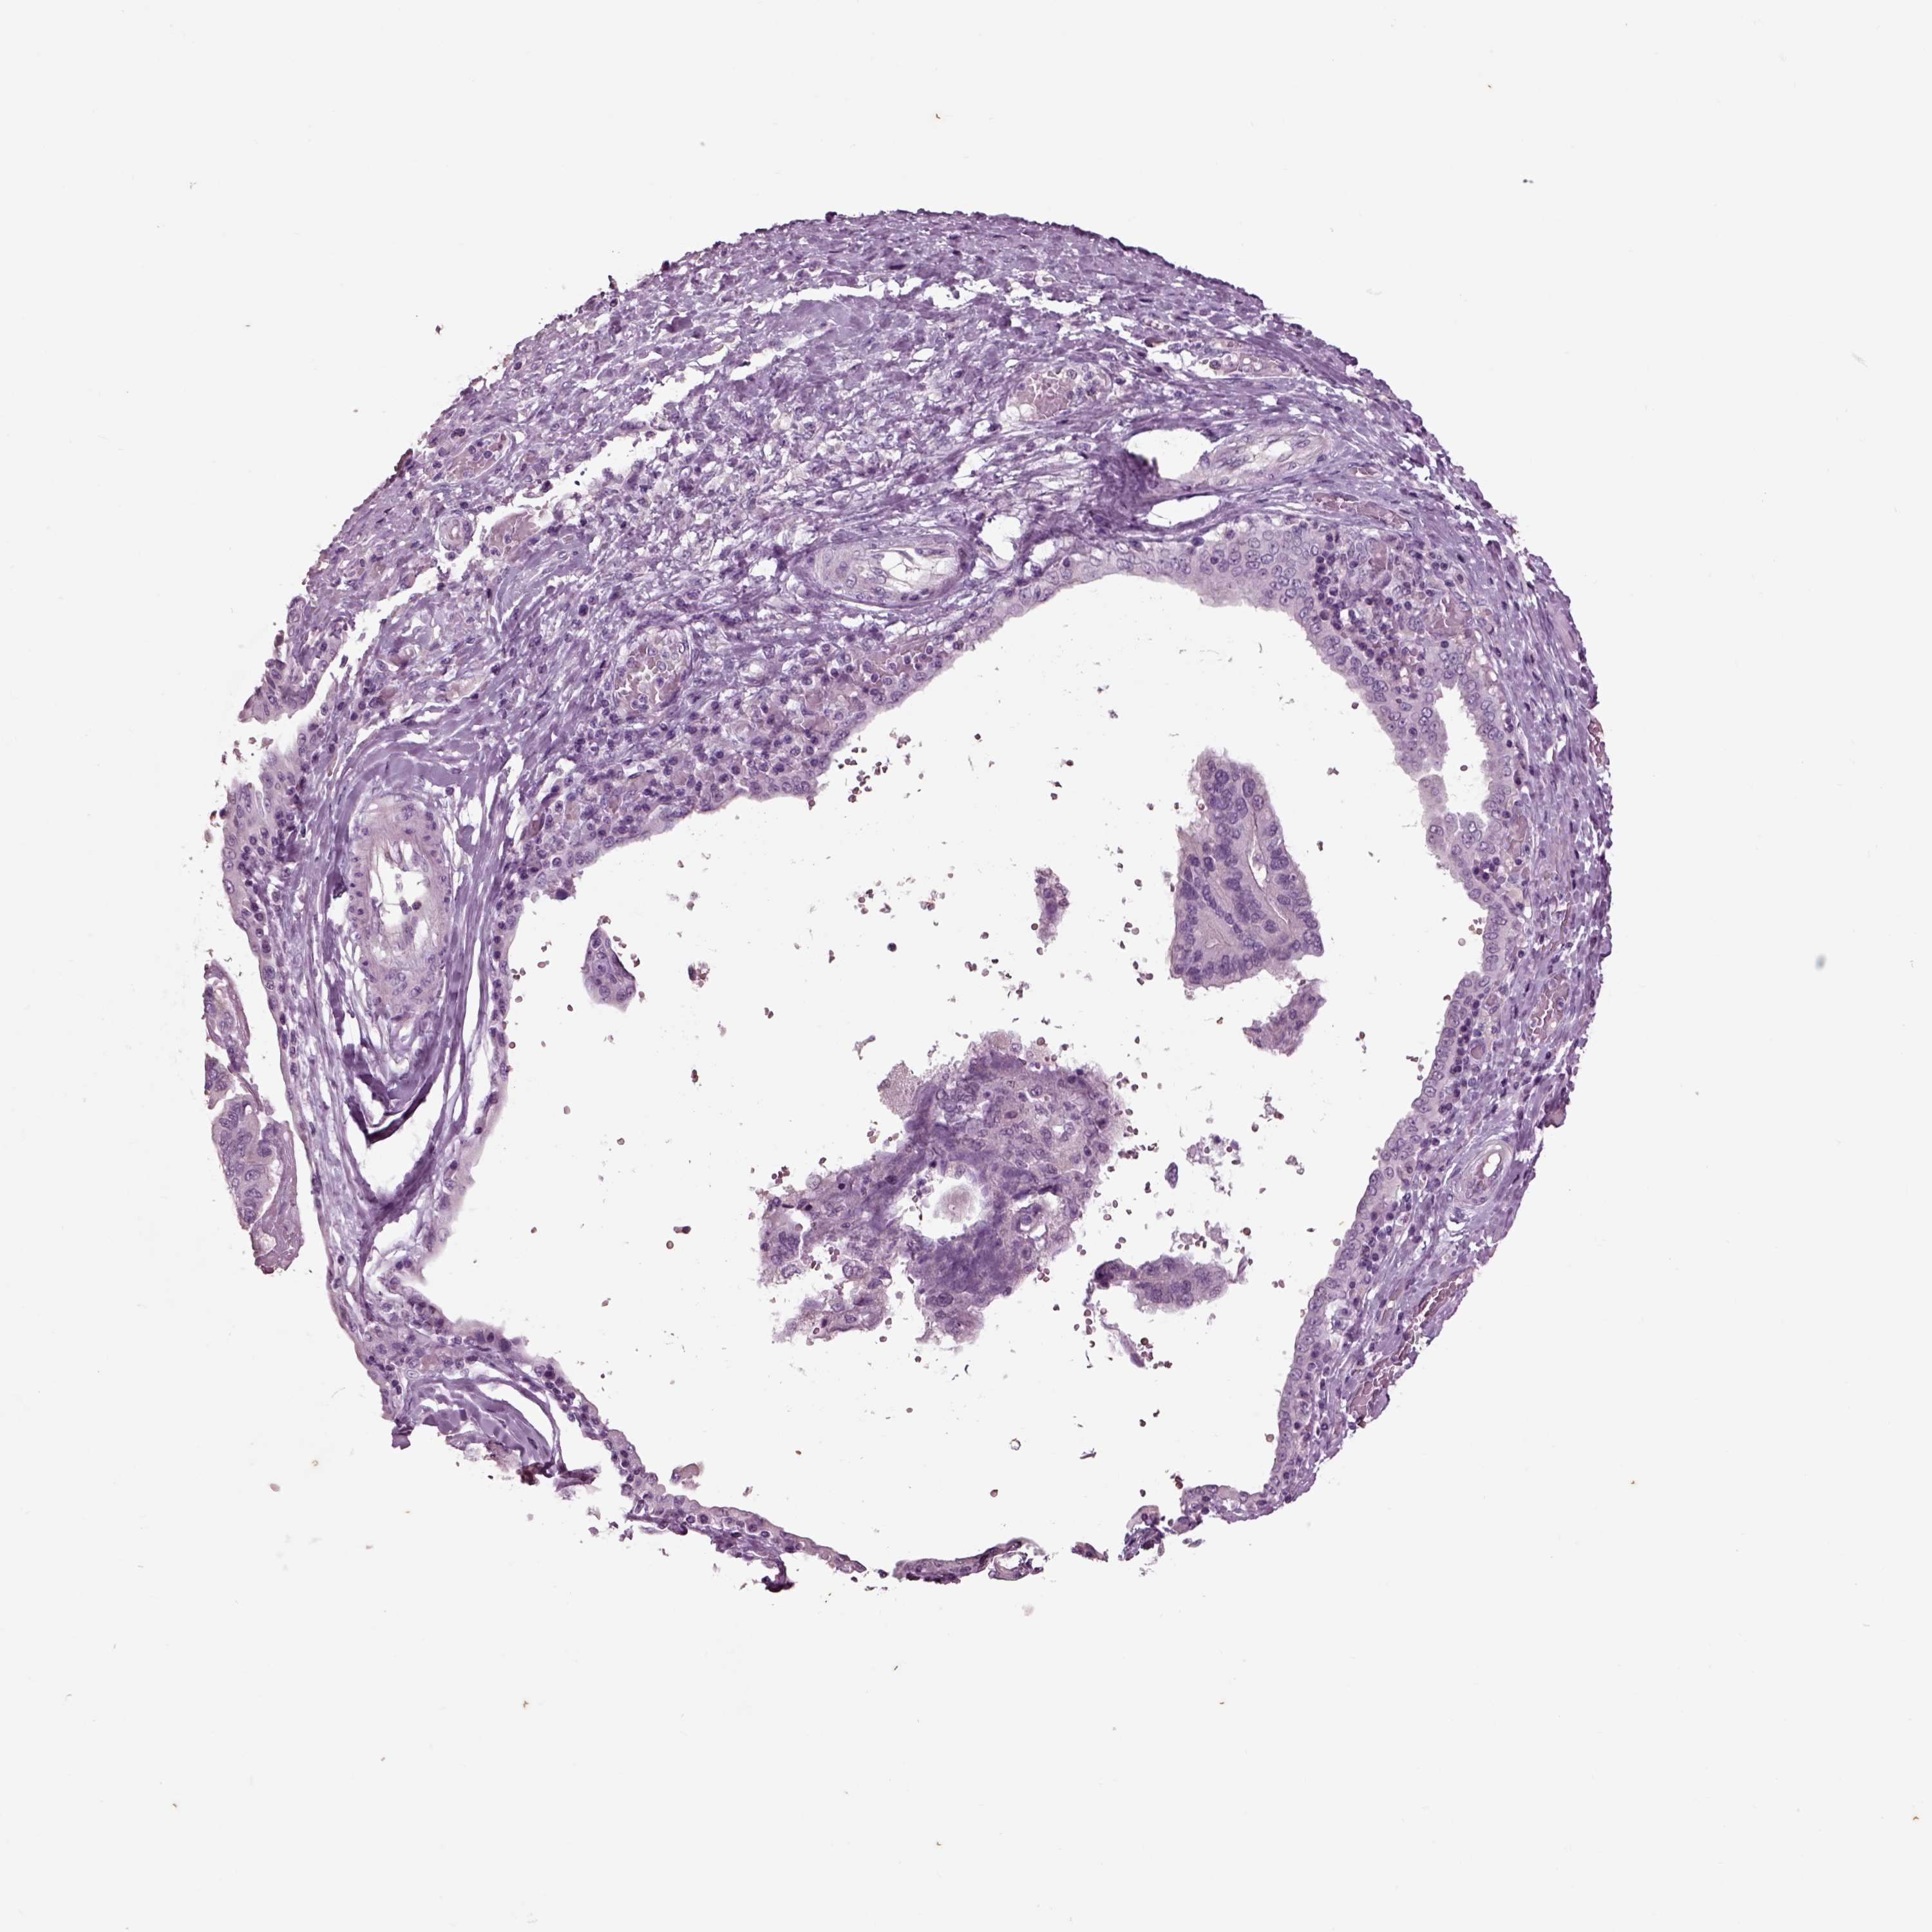

OVARIAN CANCER - Protein expressioni

A mouse-over function shows sample information and annotation data. Click on an image to view it in a full screen mode. Samples can be filtered based on level of antibody staining by selecting one or several of the following categories: high, medium, low and not detected. The assay and annotation is described here.

Note that samples used for immunohistochemistry by the Human Protein Atlas do not correspond to samples in the TCGA dataset.

Antibody stainingi

Antibody staining in the annotated cell types in the current human tissue is reported as not detected, low, medium, or high, based on conventional immunohistochemistry profiling in selected tissues. This score is based on the combination of the staining intensity and fraction of stained cells.

Each image is clickable and will lead to virtual microscopy that enables deeper exploration of all samples and also displays staining intensity scores, fraction scores and subcellular localization as well as patient and tissue information for each sample.

Antibody HPA008759

Antibody HPA012602

Antibody CAB009403

Staining

High

Medium

Low

Not detected

Cystadenocarcinoma, serous, NOS